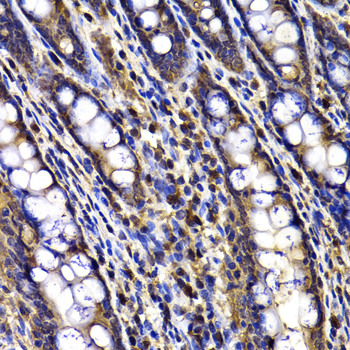

Immunohistochemistry of paraffin-embedded rat ileum using ARID3A antibody at dilution of 1:100 (x40 lens).